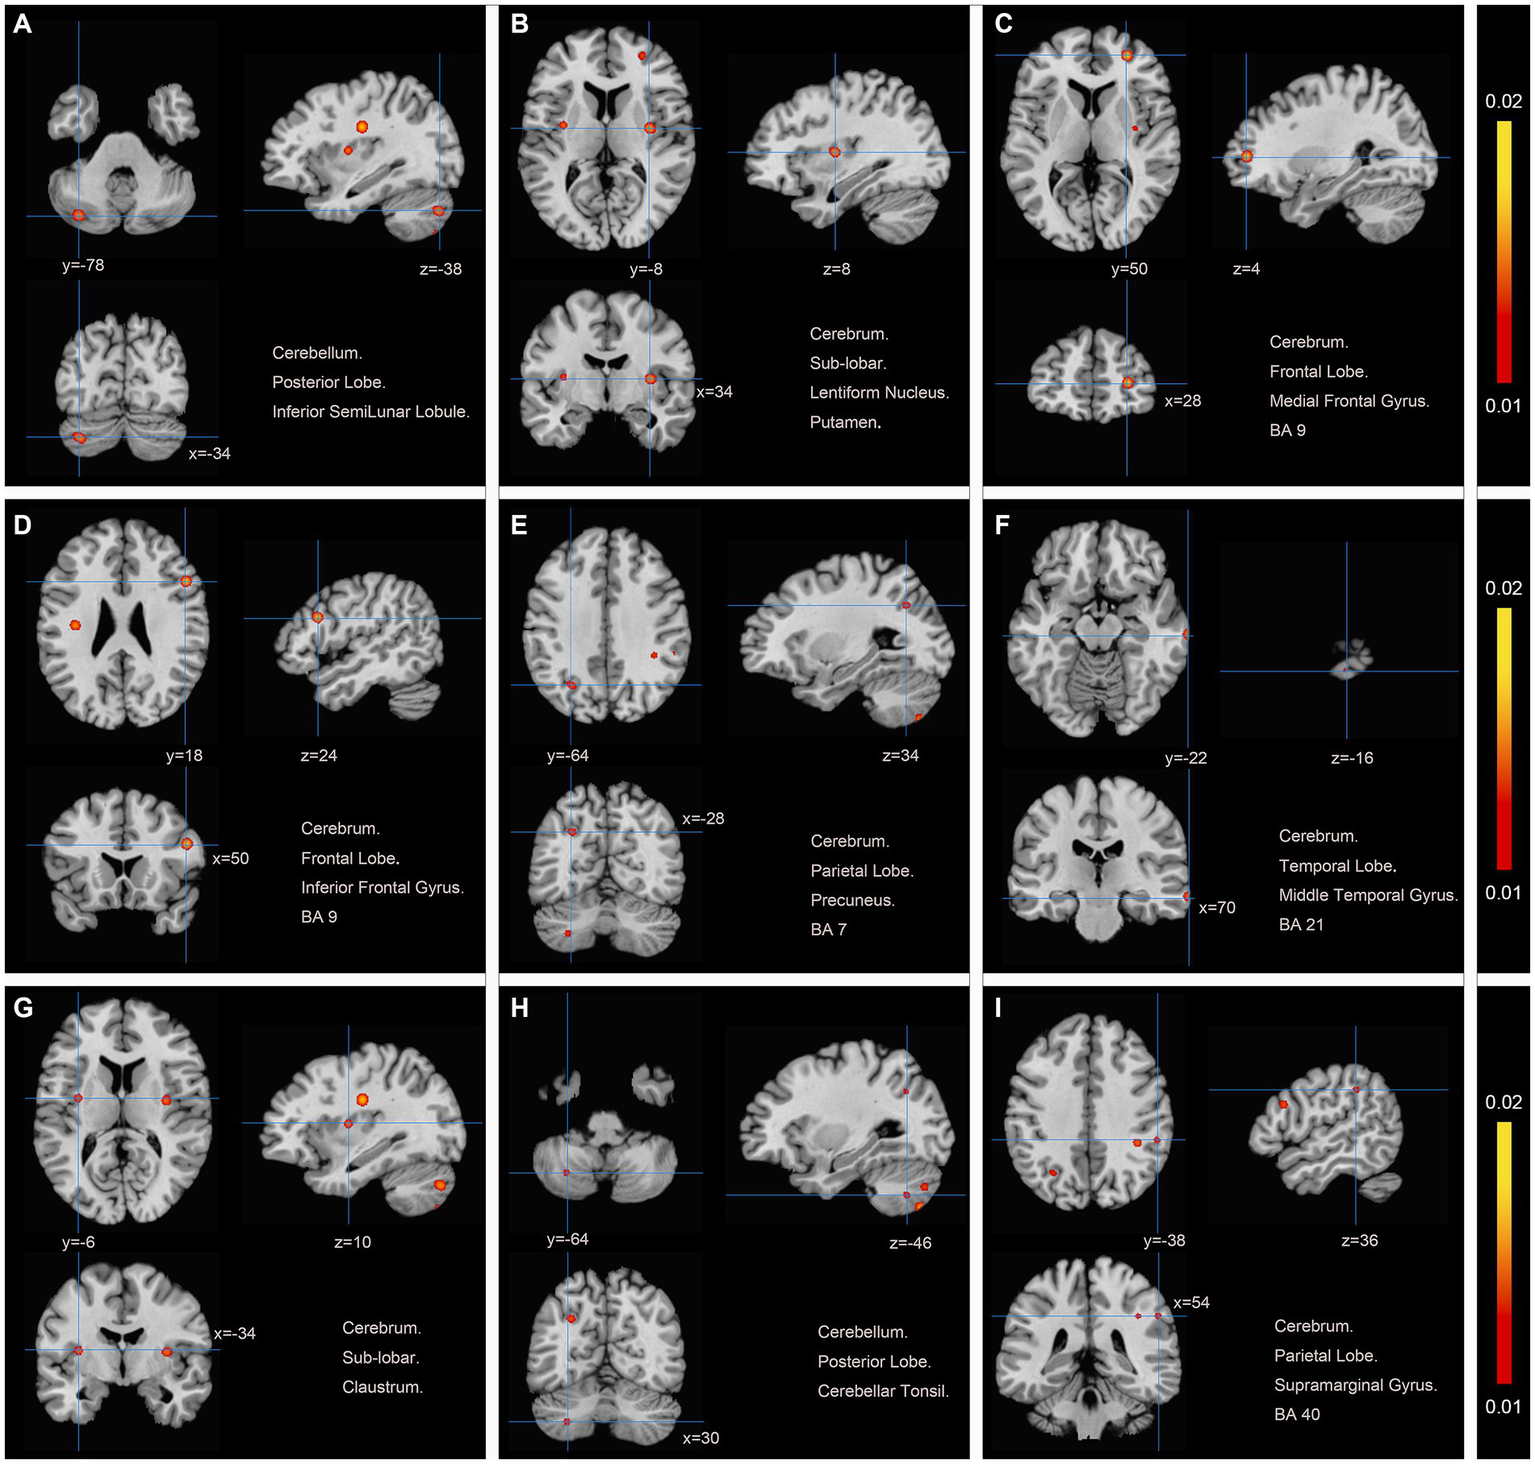

We pooled data from 12 studies (11, 19–24, 26–30) to investigate the neurological effects of acupuncture on patients with post-stroke motor dysfunction. We extracted 133 brain activation areas from 16 trials and 45 brain inactivation areas from 10 trials. A total of 9 activation clusters were found before and after acupuncture:(1) the left posterior lobe of the cerebellum; (2) the right lentiform nucleus putamen (PUT); (3) the right medial frontal gyrus (MFG); (4) the right IFG; (5) the left PCUN; (6) the right middle temporal gyrus (MTG); (7) the left claustrum (CLA); (8) the left cerebellar tonsil; (9) the right superior marginal gyrus (SMG). Three inactivated clusters were detected before and after acupuncture: (1) the right MFG; (2) the left precentral gyrus (PreCG); (3) the right PCUN. Figures 4, 5 and Table 4 show the specific analysis results.

Figure 4

Regions of brain activation in patients with pre-to post-acupuncture (Post-acupuncture > Pre-acupuncture) (A) Cerebellum Posterior Lobe Inferior SemiLunar Lobule; (B) Cerebrum Sub-lobar Lentiform Nucleus Putamen; (C) Cerebrum Frontal Lobe Medial Frontal Gyrus BA9; (D) Cerebrum Frontal Lobe Inferior Frontal Gyrus BA9; (E) Cerebrum Parietal Lobe Precuneus BA7; (F) Cerebrum Temporal Lobe Middle Temporal Gyrus BA21; (G) Cerebrum Sub-lobar Claustrum; (H) Cerebellum Posterior Lobe Cerebellar Tonsil; (I) Cerebrum Parietal Lobe Supra marginal Gyrus BA40.